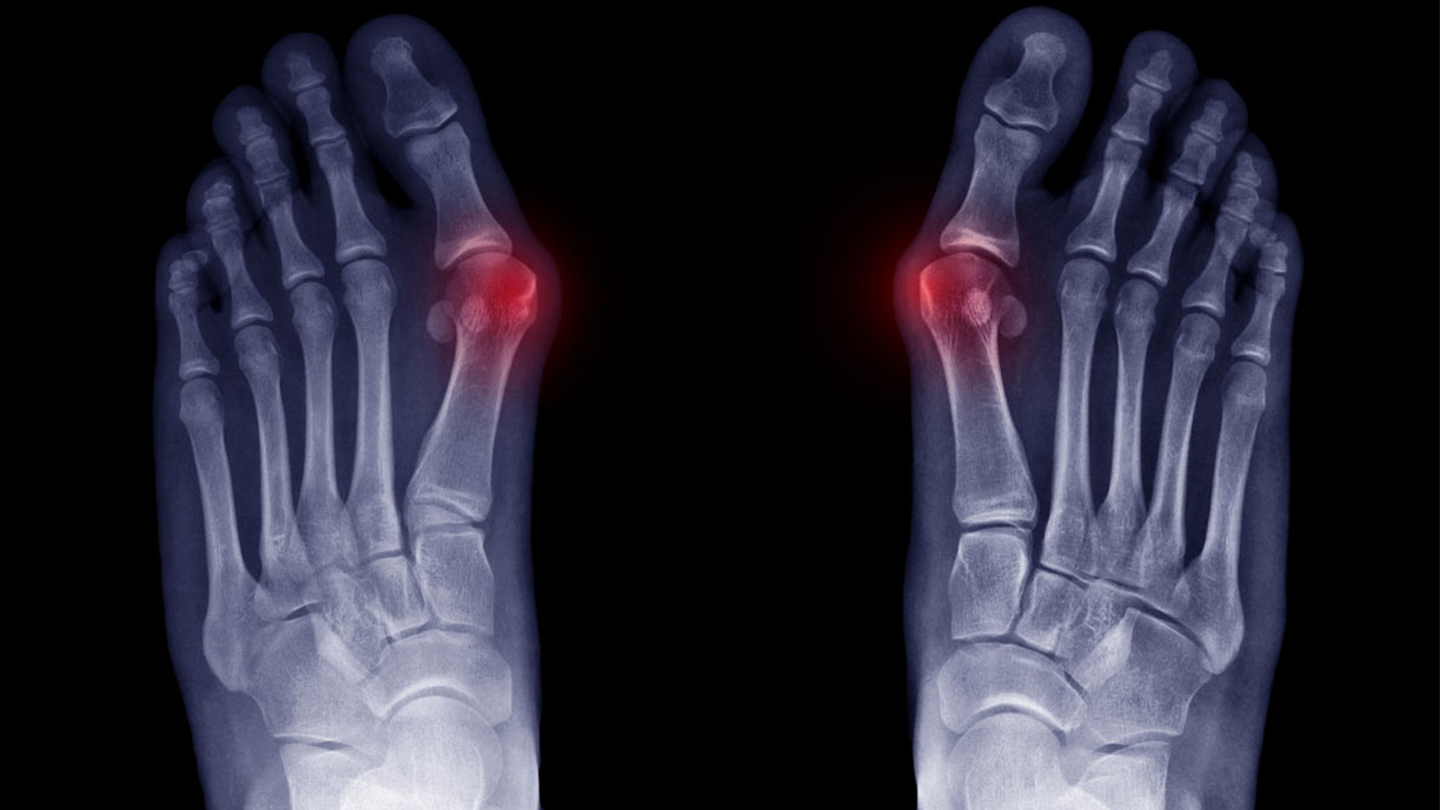

Вальгусна деформація ніг

Вальгусна деформація нижніх кінцівок — це порушення осі ніг, при якому коліна зміщуються всередину, формуючи Х-подібну форму. У такому стані змінюється розподіл навантаження: основний тиск переходить на внутрішні відділи суглобів, що запускає каскад біомеханічних порушень у всьому тілі.

2. Порушення стоп:

• прогресуюче плоскостопість

• перевантаження сухожиль